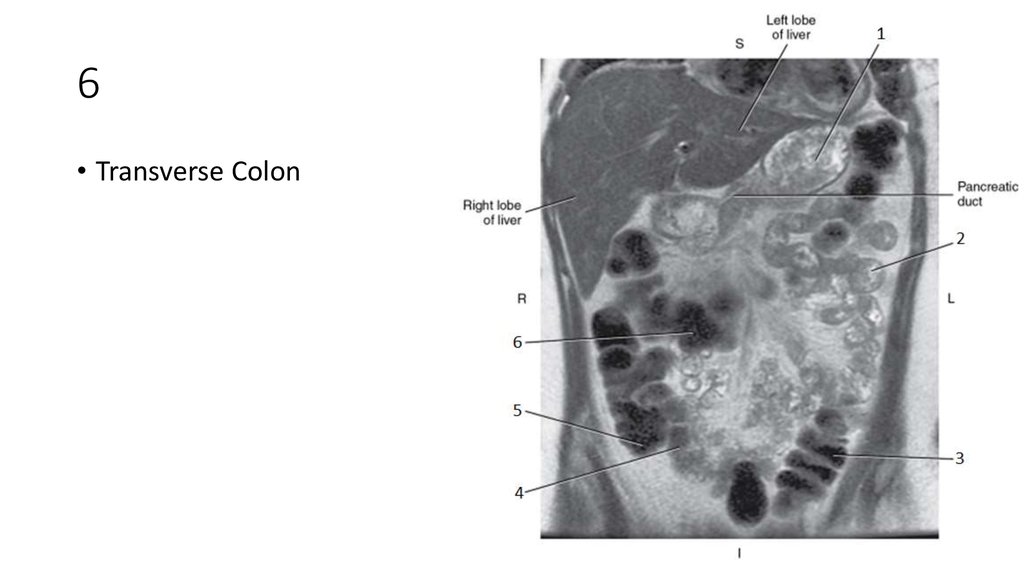

32. 1

33. 1

• Intrahepatic Ducts

34. 2

35. 2

• Pancreatic Duct

60. 6

61. 6

• Transverse Colon